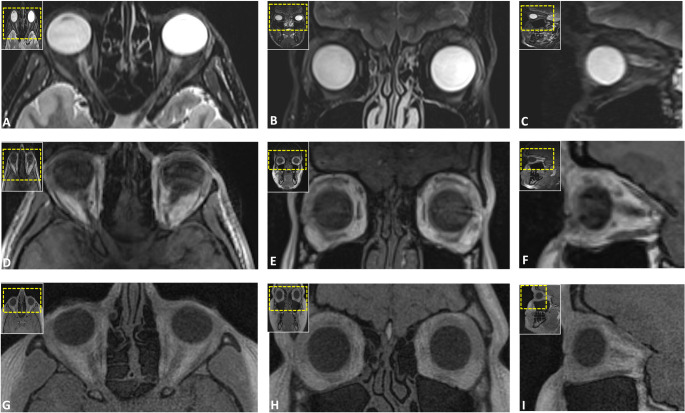

Methods: In this prospective study, healthy volunteers underwent 3T MRI using five protocols: DESS, SPACE STIR, SPACE SPAIR, T1-VIBE Dixon, and UTE. Eight trauma-prone regions, including the nasal septum, orbit, naso-orbito-ethmoidal (NOE) complex, zygomaticomaxillary complex, Le Fort regions, mandible, condyle, and dentoalveolar complex, were assessed. Image quality, artifacts, anatomical delineation, and bone-to-soft-tissue contrast were rated on a five-point Likert scale by three independent observers. Descriptive statistics and inter-rater agreement (intraclass correlation coefficients (ICCs)) were calculated.

Results: Sixteen participants (37.2 ± 12.9 years; 12 males, 4 females) were included, resulting in 80 MRI volumes and 640 regions for evaluation. UTE and VIBE-DIXON sequences achieved the highest ratings for image quality, artifact susceptibility, and anatomical delineation across most fracture-prone regions (ICC: 0.793-1; all p < 0.001). UTE excelled in visualizing NOE and Le Fort regions, while VIBE-DIXON performed best in mandibular and orbital imaging. Bone-to-soft-tissue contrast was highest in UTE and VIBE-DIXON, highlighting their diagnostic potential in simultaneous soft and hard tissue imaging. Inter-rater agreement was consistently high (ICC: 0.772-0.976; all p < 0.001).